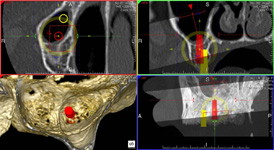

NewTom Implant Planing

Jedná se o plánovací program, který využívá dat získaných při vyšetření pomocí přístroje New Tom. Tento program umožňuje tříprostorovou počítačovou simulaci při plánování pozic implantátů.

Součástí programu je i databáze, ve které mohou být uloženy všechny typy implantátů od všech výrobců, včetně jejich délek, průměrů i tvarů.

Lékař si vytvoří všechny typy zobrazení potřebných pro naplánování – tedy 2D snímky (panoramatický), příčné řezy i 3D model.

Vidí zde i důležité anatomické útvary – čelistní dutinu, průběh nervu atd. Po proměření množství kosti – šířky i výšky vybere z databáze vhodný typ implantátu a umístí ho do požadované lokality.

Ihned vidí jeho pozici ve všech 3 rovinách a na všech snímcích i 3D modelu. Může upravovat podle potřeby jeho pozici, sklon atd.

Všechny vybrané a správně umístěné simulované implantáty se ukládají do „počítačové karty“ pacienta s jejich pozicí, délkou, průměrem, typem i sklonem.

Lékař i pacient tedy ještě před vlastní operací vidí, jak by mělo ošetření probíhat a vypadat.